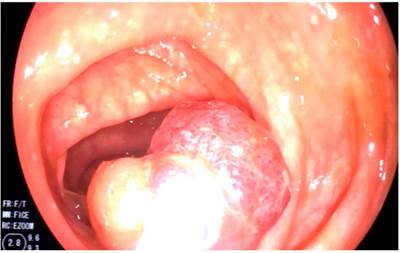

During his hospital stay, the patient presented an exacerbation of the symptoms, which was then worsened by hematochezia. For this reason, a total colonoscopy was requested. In the colonoscopy a large 40 mm pedunculated polyp was observed with a long pedicle of approximately 30 mm in the sigmoid colon, showing a prolapse caused by peristalsis that generated an obstruction of the colonic lumen (Figures 1,2,3y4). The polyp’s head was eroded, which was a possible cause of hematochezia.

Then, performing an endoscopic polypectomy was decided. In addition, because of the size of the pedicle, a hemostatic loop (endoloop) was inserted. The polypectomy loop was then used, and the polyp was resected (Video 1).